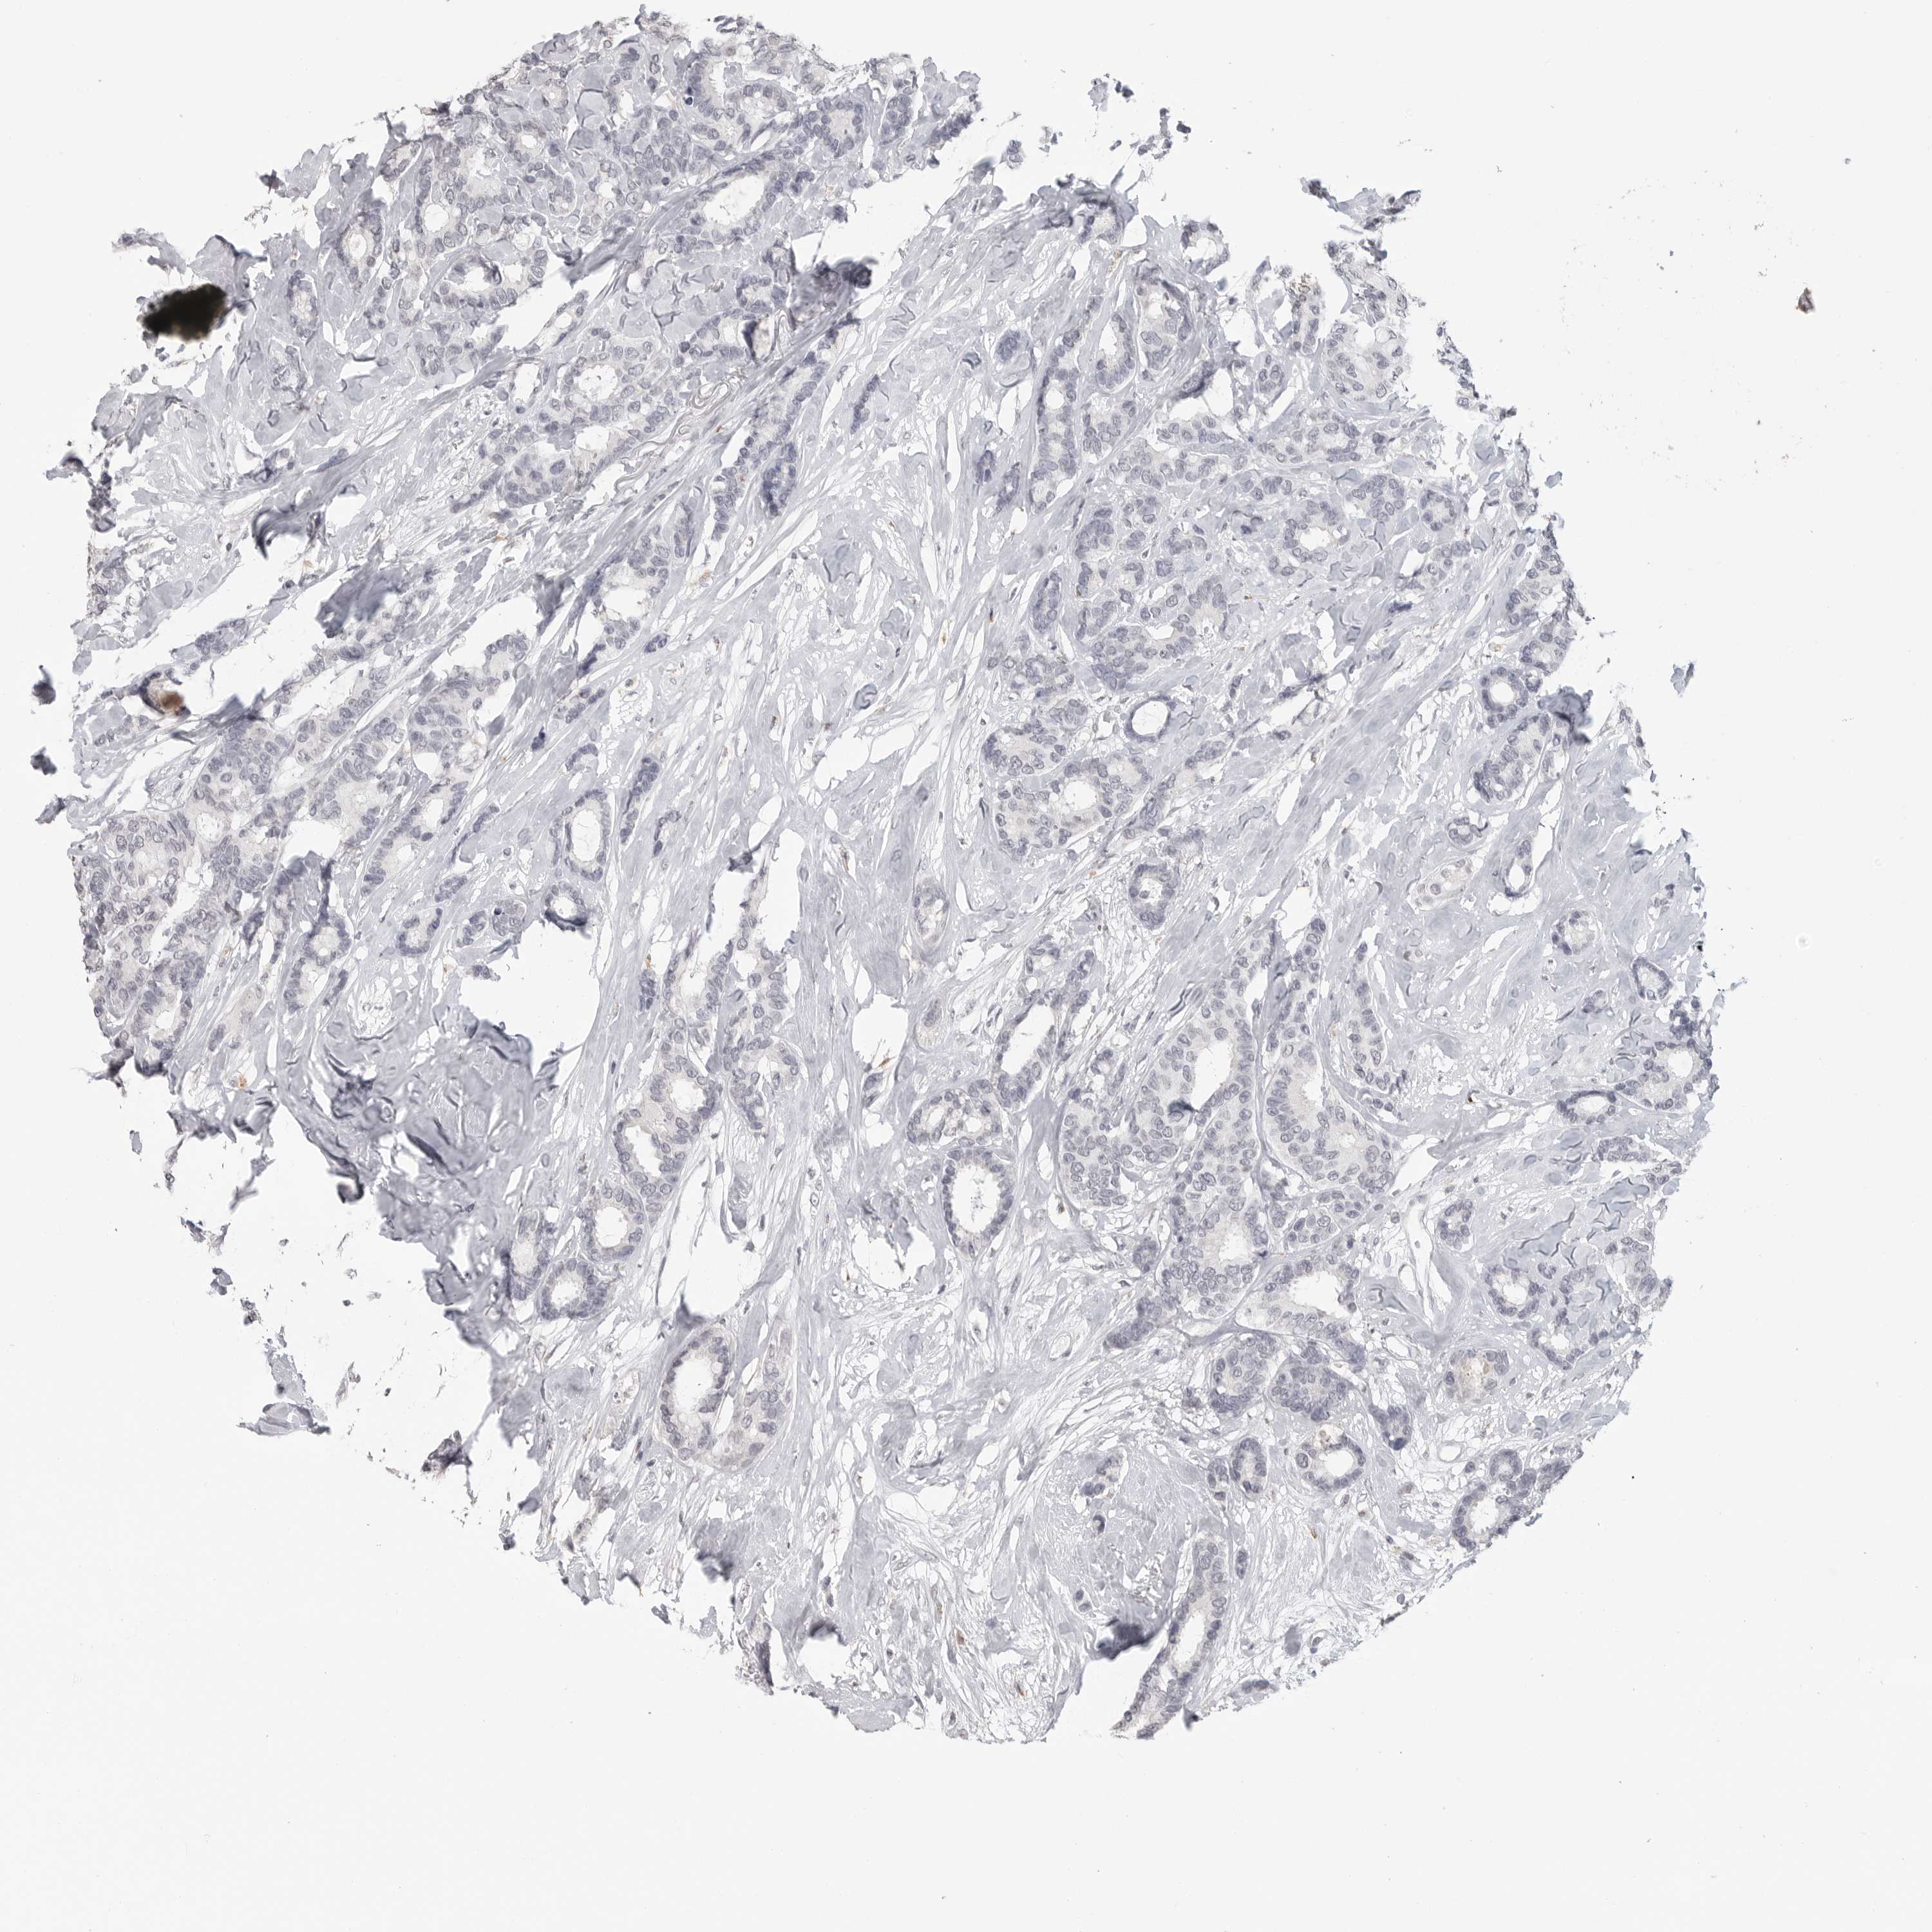

CANCER BREAST CANCER Show tissue menu

BRCA TCGA BRCA VALIDATION PROTEIN EXPRESSION